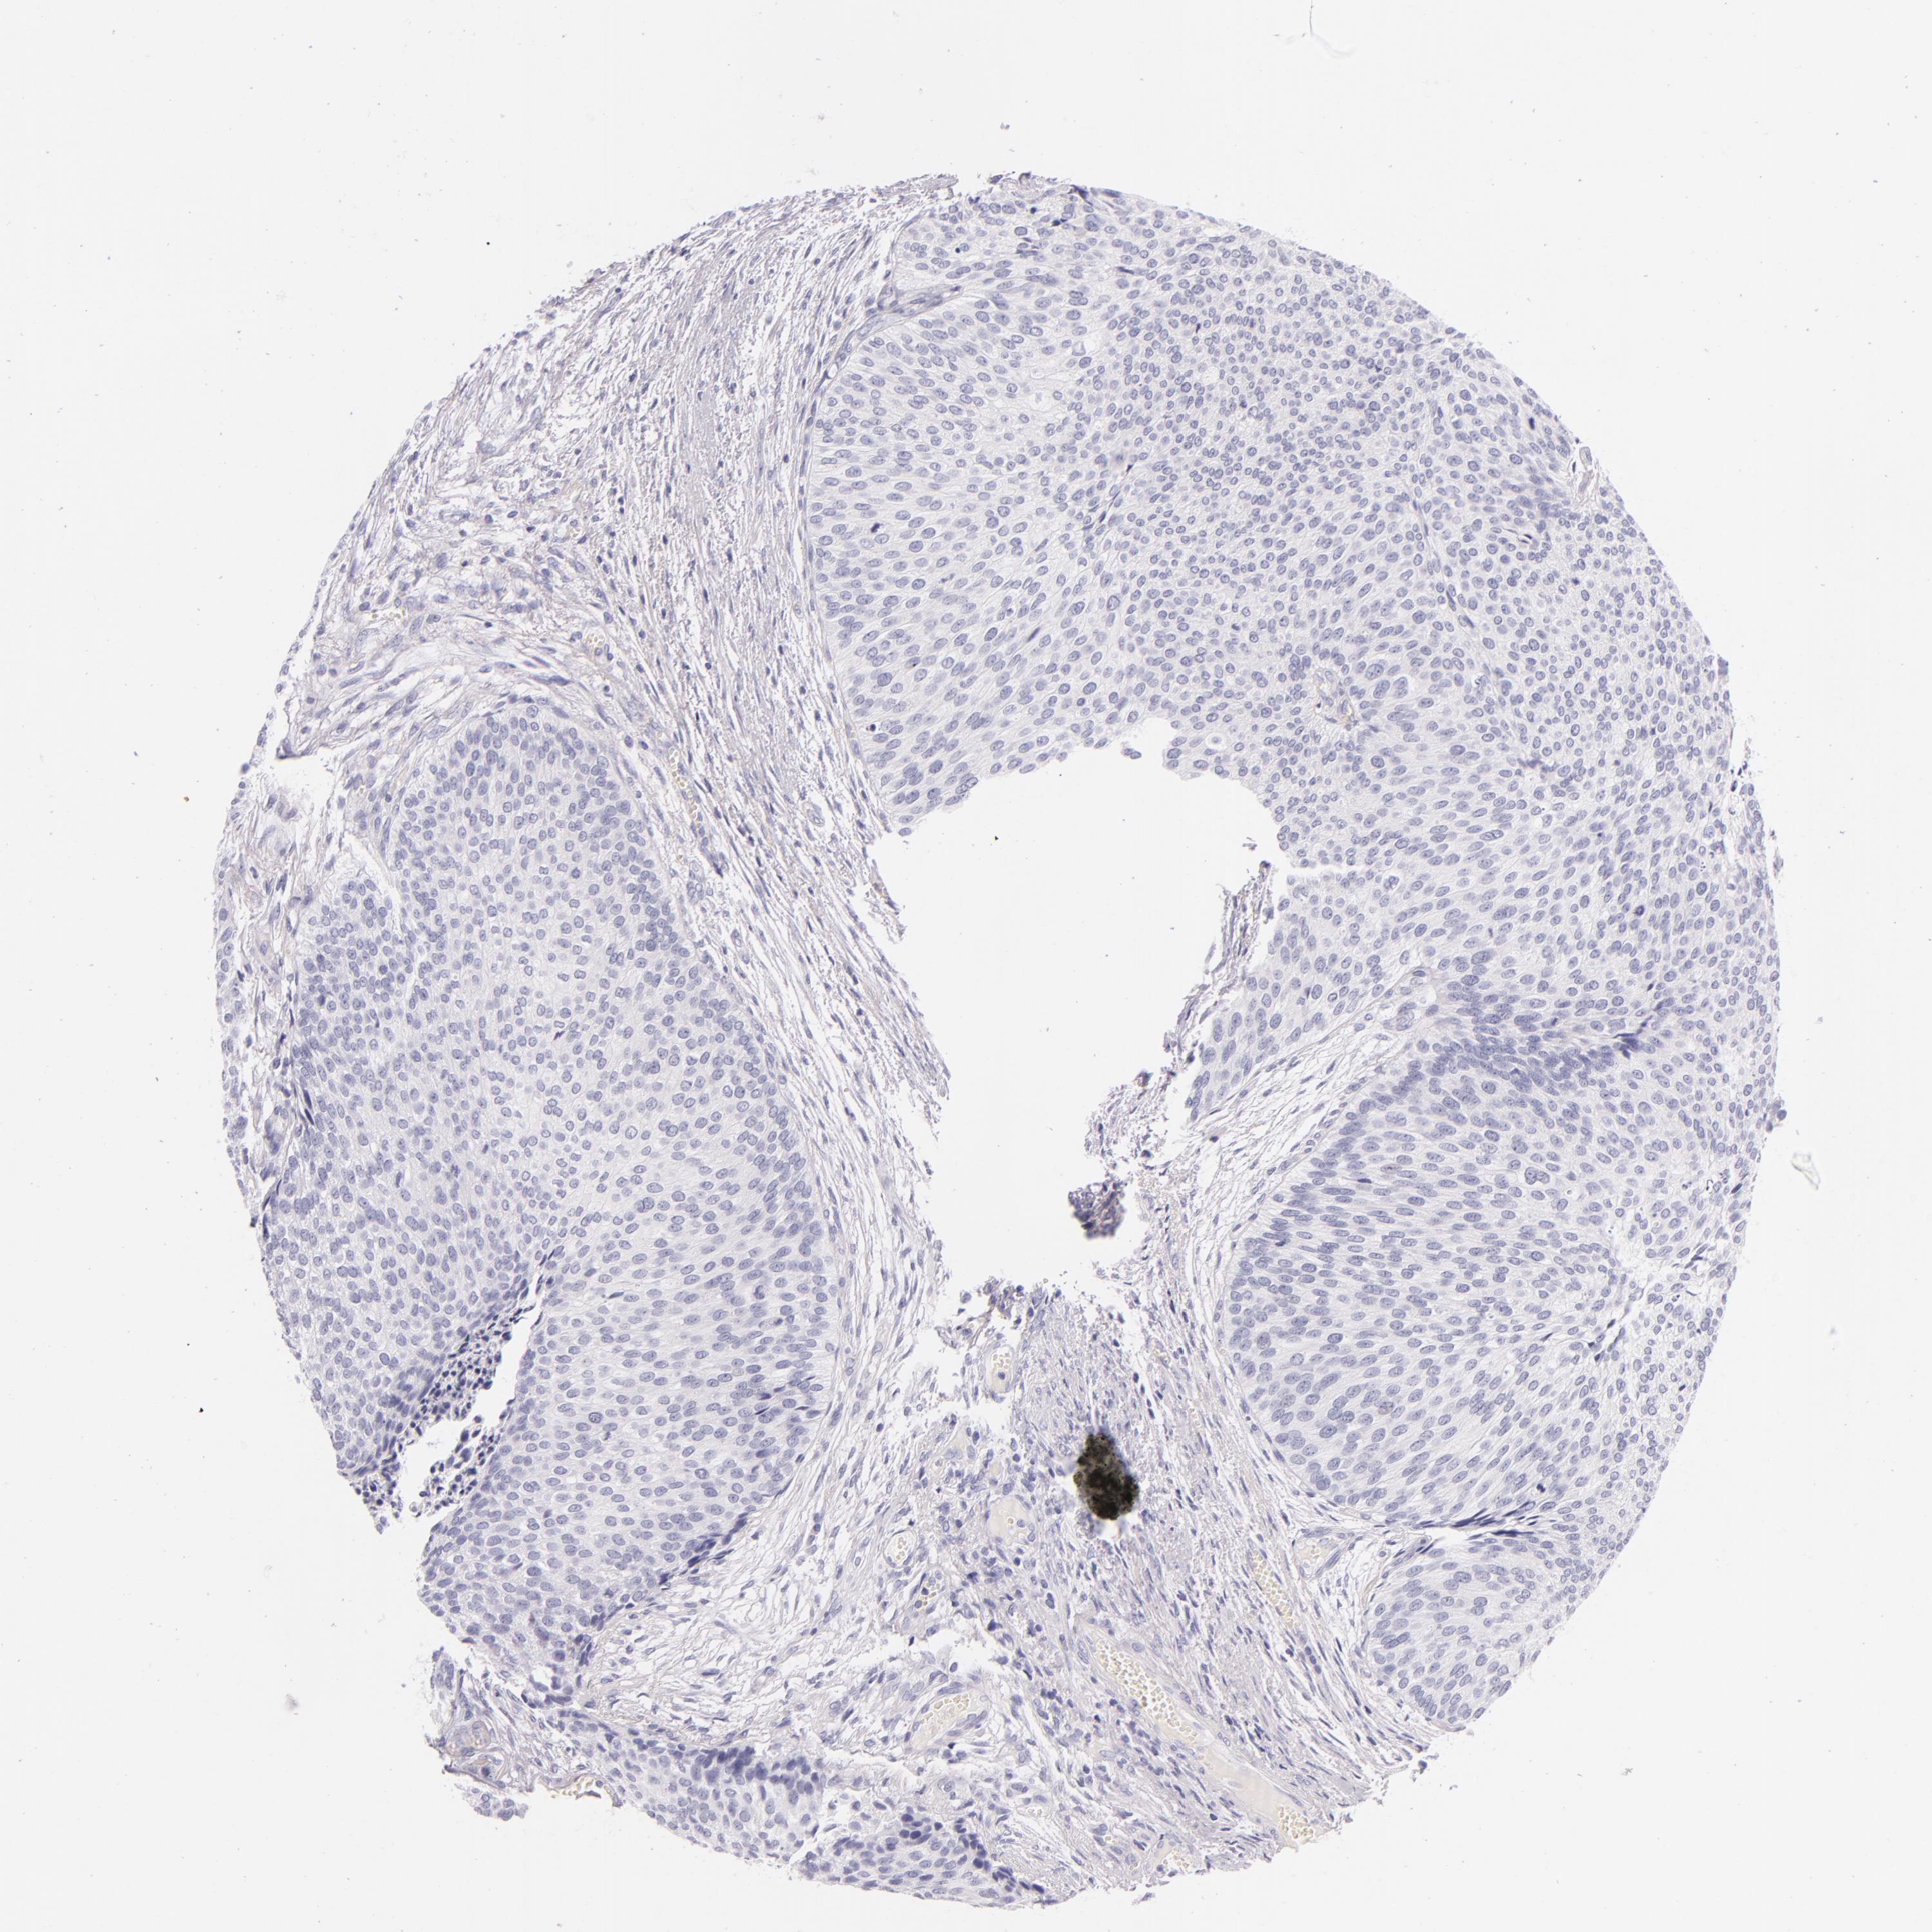

UROTHELIAL CANCER - Protein expressioni

A mouse-over function shows sample information and annotation data. Click on an image to view it in a full screen mode. Samples can be filtered based on level of antibody staining by selecting one or several of the following categories: high, medium, low and not detected. The assay and annotation is described here.

Antibody stainingi

Antibody staining in the annotated cell types in the current human tissue is reported as not detected, low, medium, or high, based on conventional immunohistochemistry profiling in selected tissues. This score is based on the combination of the staining intensity and fraction of stained cells.

Each image is clickable and will lead to virtual microscopy that enables deeper exploration of all samples and also displays staining intensity scores, fraction scores and subcellular localization as well as patient and tissue information for each sample.

Antibody HPA008057

Antibody CAB002059

Urothelial carcinoma, High grade

Urothelial carcinoma, NOS